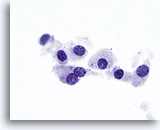

Onbepaalbaar voor maligniteit

Deze catergorie omvat in ons lab ook monsters waarvan de voorspellende waarde van maligniteit bij histologie minder dan 50% is (meestal minder dan 30%) en hoger dan 10%.[6, 7] Dit omvat die monsters die een paar kenmerken vertonen van papillair carcinoom, maar die onvoldoende zijn voor een diagnose. [7] De positieve voorspellende waarde hiervan varieert in de literatuur van 20 tot 54%. [7, 9, 10, 11] Deze laesies vertegenwoordigen vaak de folliculaire variant van papillair carcinoom. In deze diagnostische categorie vallen ook folliculaire en Hürthle celneoplasma’s, die worden gekenmerkt door weinig colloïde en folliculaire cellen in microfollikels en opeengepakte groepen of losse Hürthle-cellen. De positieve voorspellende waarde van deze laesies voor een carcinoom varieerde in de literatuur van 2 tot 91%,[6, 9, 10, 12, 13, 14, 15, 16, 17, 18, 19, 20, 21, 22, 23, 24, 25, 26, 27]waarschijnlijk als gevolg van verschillende definities van deze termen en wisselende criteria die worden gebruikt voor het schema en bij de histologische diagnose. Bij de meeste rapporten is deze waarde minder dan 30%. [10, 15, 22, 24, 27]